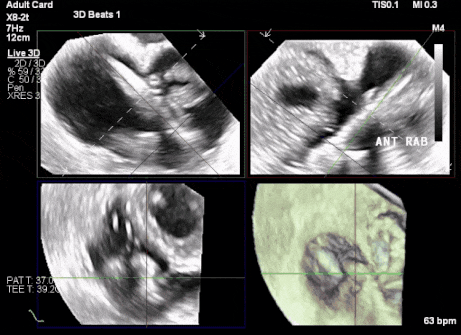

術中DSA顯示起搏器導線的干擾,右心室造影確定瓣環位置,操作空間小

術后超聲顯示人工瓣膜穩定性良好,瓣葉啟閉正常